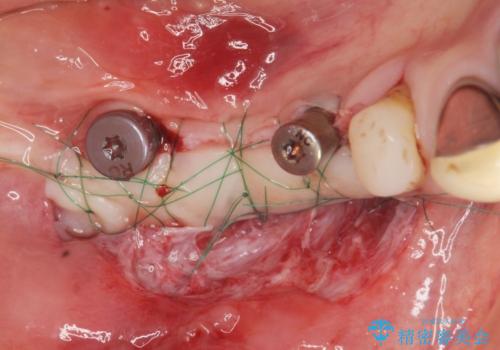

長年の義歯の使用により骨の幅は非常に薄くインプラントを埋入するには大規模な骨の造成が必要な状態です。

また骨の問題だけでなく、完成後に歯ブラシがしやすいよう歯ぐきの移植も行いよりインプラント周囲の環境が安定するよう環境を整える治療計画を立てます。

インプラントを埋入するには十分な骨の量が必要で、吸収して少なくなってしまった場合でも造成できる場合があります。

また、機能したインプラントを長持ちさせるために清掃性を高めるために硬い歯ぐきを移植することは非常に有効です。